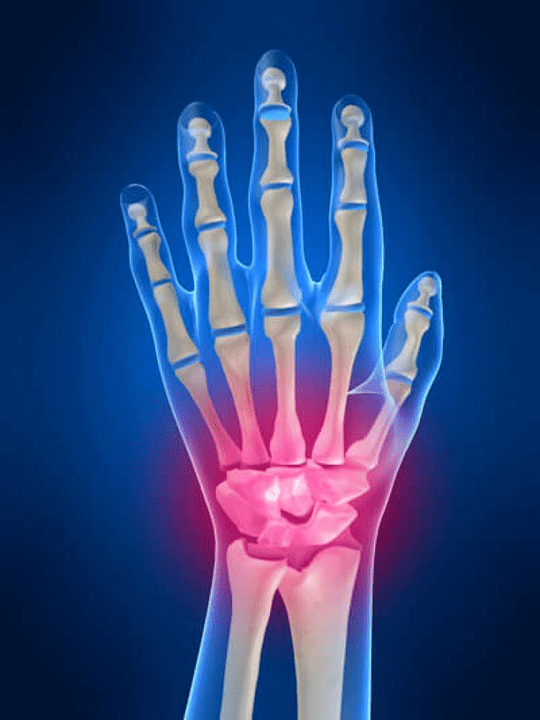

Dureri articulare Degetele sunt un semn indispensabil al oricărei patologii comune în care componentele structurale ale acestor articulații sunt deteriorate. În primul rând, durerea în zona acestor articulații poate fi asociată cu diverse boli autoimune (Luster roșu sistemic, artrită reumatoidă, artrită psoriazică, etc.) în care factorii imuni provoacă deteriorare propriilor țesuturi articulare.

Următorul motiv principal care poate iniția durere În articulațiile degetelor, pot exista răni (vânătăi, luxații, fracturi osoase, ligamente) Durerea în aceste articulații poate fi, de asemenea, provocată de modificări degenerative care apar în țesuturile lor articulare. Acest lucru poate fi adesea observat cu osteoartrită.

Ce structuri pot deveni inflamate în articulațiile mâinilor?

Inflamarea este un proces patologic tipic caracteristic acelor țesuturi și organe care au fost deteriorate din orice motiv. Merită să ne amintim că, în majoritatea cazurilor, fiecare boală (De exemplu, gută, artrită reumatoidă etc.) sau traume care deteriorează articulațiile mâinilor într -un anumit grad sau altul, afectează nu numai cele articulare, ci și perioatorul (nervi, mușchi, tendoane, grăsime subcutanată, piele) structuri.

Următoarele structuri articulare pot deveni inflamate în articulațiile mâinilor:

- cartilaj comun;

- Stoarcerea țesutului osos;

- capsulă comună;

- Ligamente comune.